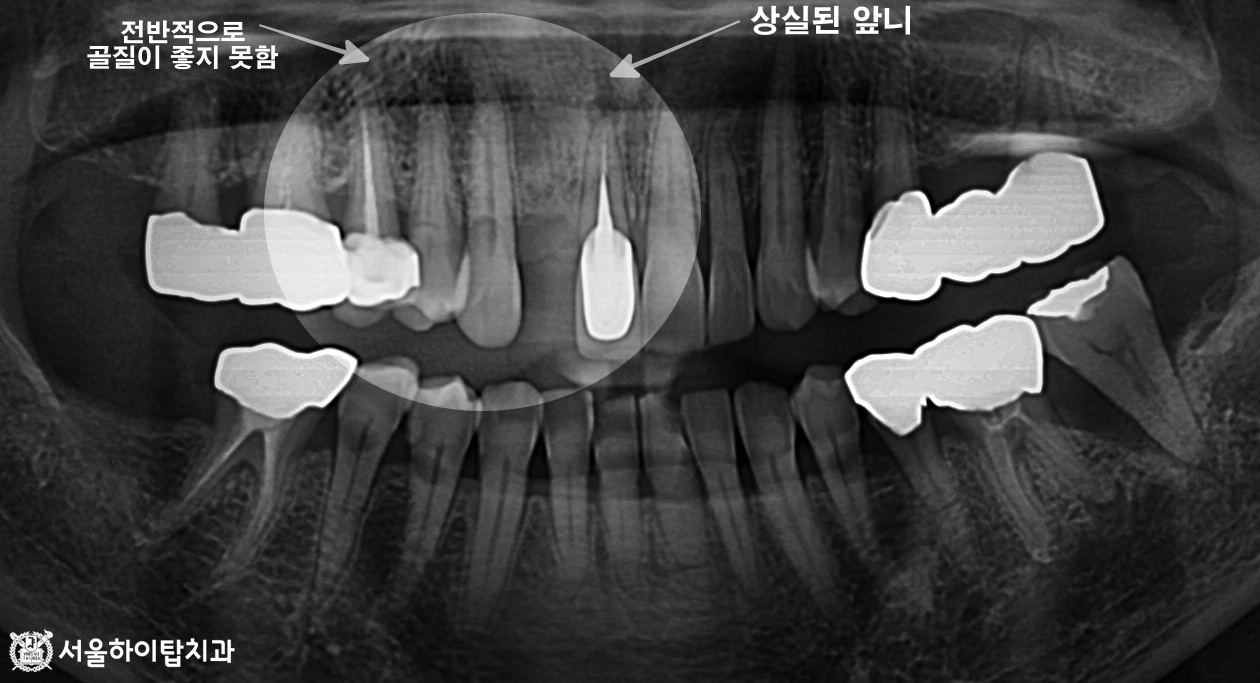

십정동 치과 어금니 상실 후 CT 기반 정밀 진단 후 진행한 당일 즉시 임플란트 진행 과정 동암역 치과, 불편한 앞니 바로 신경치료할까요? 검사부터 치료까지 (치근단 염증 · PFM 크라운) 주안역 치과 치아 흔들림(동요도 3도) 발치 후 임플란트 진행 과정 부평 치과 치아 머리·목 부분에 진행된 충치, 신경치료 과정 및 장기적 파절 가능성 안내 십정동 치과 앞니에서 파절이 쉽게 일어나는 부위가 있다? 절단연 파절 후 레진 수복 과정 간석오거리역 치과 치수까지 침범한 충치, 발치 후 임플란트 진행 과정 (정기검진과 조기 치료의 중요성) 만수동 치과 80대 고령환자, 심한 충치 치아 발치 후 임플란트 수술 과정 (발치가 필요한 충치?) 백운역 치과 신경치료 후 앞니 치아가 파절되기 쉬운 이유가 무엇일까? 임플란트 수술 과정 주안동 치과 70대 고령 환자│뿌리까지 이어진 치아 파절의 원인과 임플란트 수술 과정 간석동 치과│치주염으로 인한 골 흡수와 치아 흔들림, 뼈 이식을 동반한 임플란트 치료 과정 부평 치과 심한 치아 통증 엑스레이에서 보이지 않는 치수염? 신경치료와 크라운 수복 과정 만수동 치과|성장기 치아 상실, 왜 성인이 되어 임플란트를 했을까요? (상악동 거상술 동반) 십정동 치과 상실된 치아가 불러오는 연쇄적 문제? 치조골 흡수와 기울어진 어금니, 뼈이식 동반 임플란트 과정 동암역 치과 : 균형 잡힌 저작이 중요한 이유, 전반적으로 손상된 치아 및 잇몸 임플란트를 통해 저작 기능 개선 간석역 치과 치주염으로 인한 치조골 흡수, 치아 파절 및 마모까지 임플란트 가상 시뮬레이션을 통한 안전한 수술 과정 1 2 Next Archives 2026년 4월 2026년 3월 2026년 2월 2026년 1월 2025년 12월 2025년 11월 Categories 미분류 신경치료 심미 치료 임플란트 BACK TO TOP